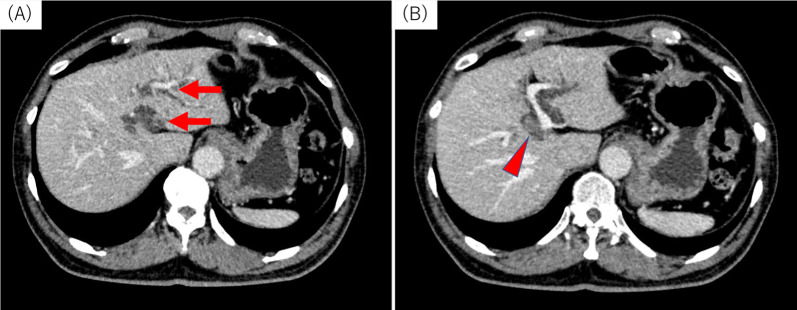

A 69-year-old man was referred to our hospital for the evaluation and dilation of an intrahepatic bile duct (IHBD) mass. His initial laboratory values were as follows: total bilirubin, 1.0 mg/dL; direct bilirubin, 0.2 mg/dL; aspartate aminotransferase, 36 mg/dL; alanine aminotransferase, 50 mg/dL; alkaline phosphatase, 358 U/L; and γ-glutamyl transferase, 260 U/L. The tumor marker levels (including carcinoembryonic antigen and carbohydrate antigen 19–9) were within the normal ranges. Contrast-enhanced computed tomography (CT) revealed IHBD dilation in the left hemiliver (Fig. 1A) and a mass in the left hepatic duct (LHD) (Fig. 1B). The posterior segmental branch of the hepatic duct (PHD) draining into the LHD was also dilated. There was no evidence of distant metastasis. Magnetic resonance cholangiopancreatography (MRCP) revealed a 2-cm intraductal mass located between the LHD and PHD. Endoscopic retrograde cholangiography findings indicated the presence of a defect in the LHD and dilated LHD (Fig. 2), and bile duct brushing cytology was performed. Cytology showed atypical cells in the specimen from the mass, but the diagnosis was not clear.

Fig. 1.

Contrast-enhanced computed tomography findings for the primary lesion. A Dilation of the intrahepatic bile duct was noted (arrow). B A mass of approximately 10 mm in diameter with sight enhancement was noted in the left hepatic duct (red arrowhead)